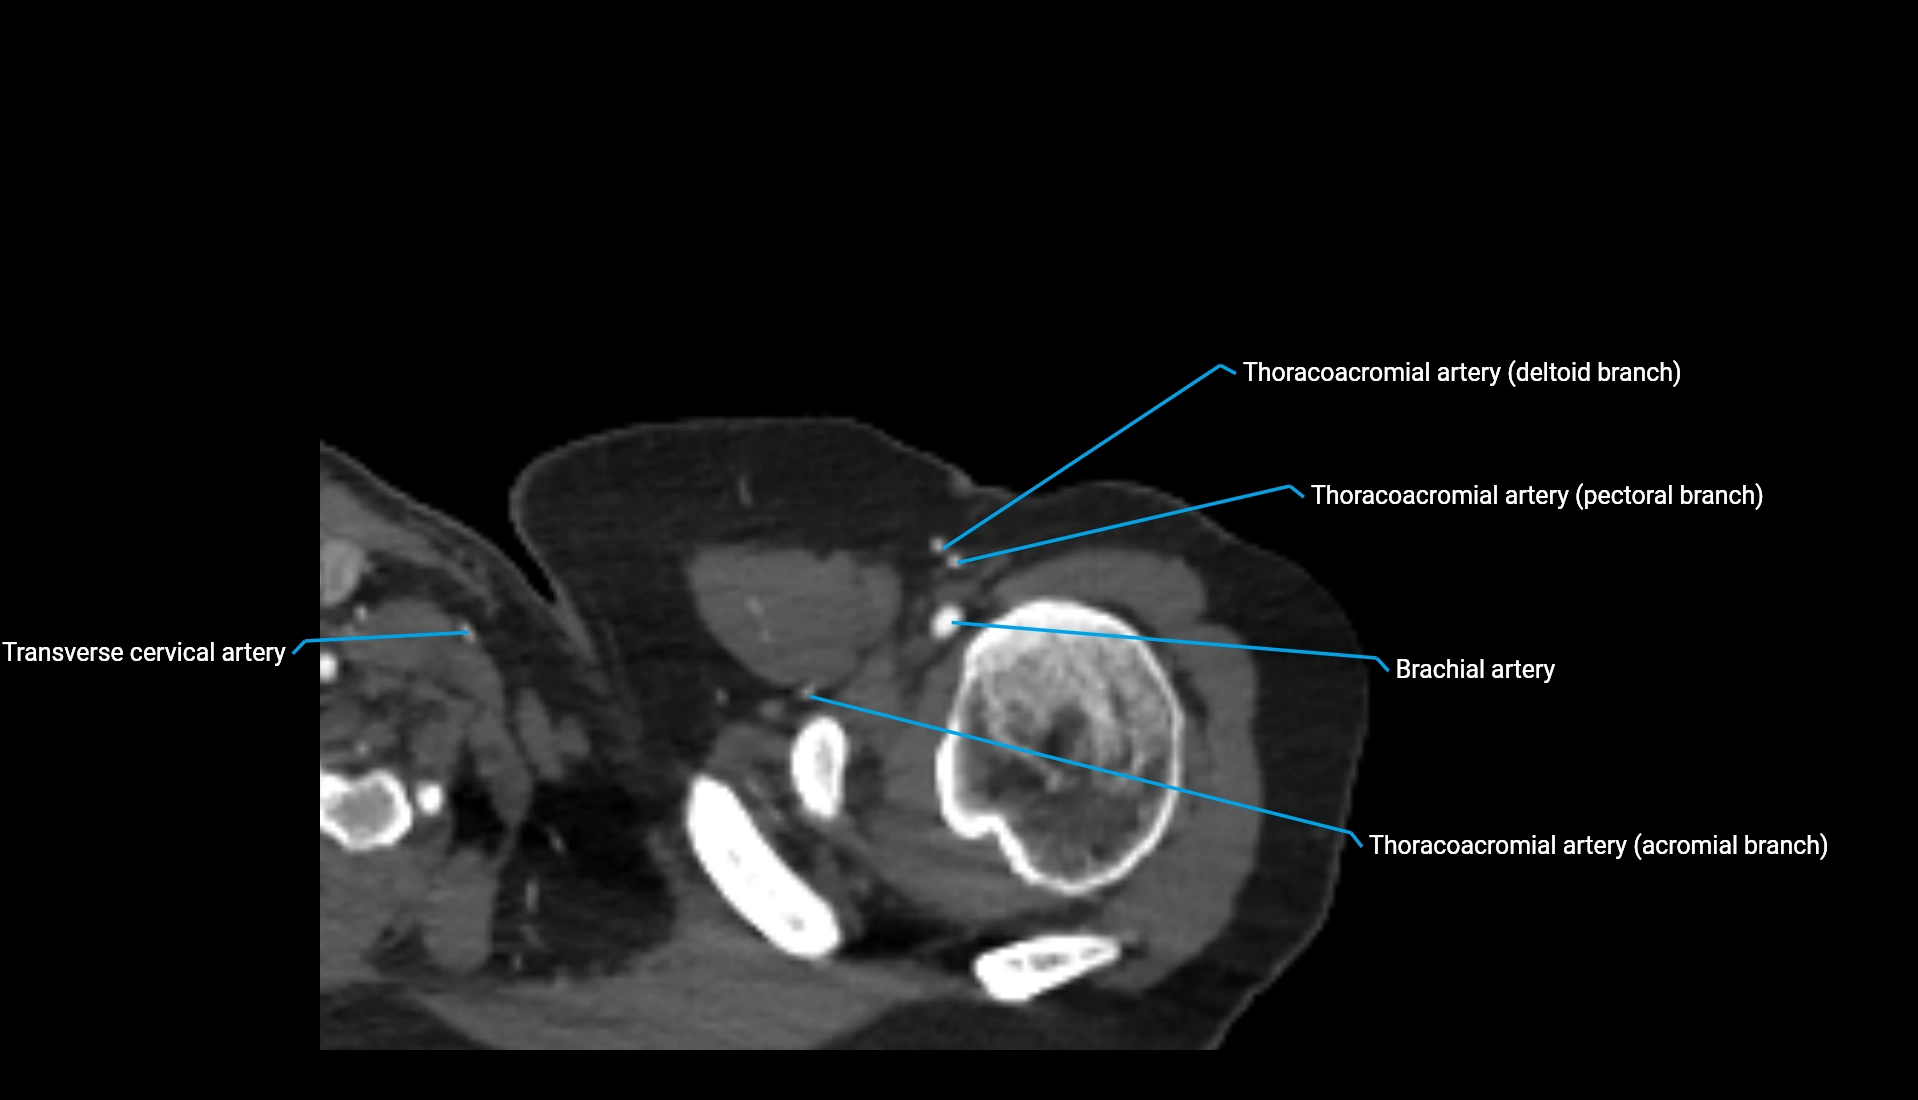

CT Appearance

Non-Contrast CT:

• Cortex: High-density, sharply defined

• Subchondral bone: Dense cancellous matrix

• Articular surface: Smooth concave contour articulating with the capitellum

• Excellent for evaluating bone integrity, alignment, and subtle fractures